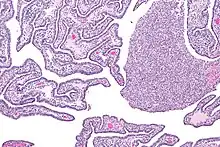

| Micrograph of acute and chronic salpingitis. H&E stain. | |